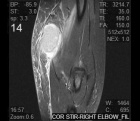

14 yo female w/ 1 month history of increasing mass in right medial elbow. C/o associated pain, edema and recent purulent drainage with incidental trauma to the mass. Denies previous h/o trauma. Denies fever, malaise or other associated constitutional symptoms.

PE: RUE with significant edema and 3cm palpable soft tissue mass at right medial elbow. Mild erythema is present. ROM limited secondary to pain. Skin is intact. Multiple, benign, faint scars present along distal dorsal forearm. NVI. Shotty cervical lymph nodes w/o inguinal or axillary lymphadenopathy.